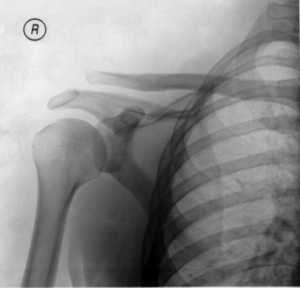

| A Separated Shoulder XRay modified to easily show bones. Notice the separation between the end of the collarbone and the scapula. | |

A separated shoulder (also known as acromioclavicular separation, AC separation), is a common injury to the acromioclavicular joint. It is a joint dislocation, but it is not called a dislocated shoulder, as that term refers to a glenohumeral joint (shoulder joint) dislocation. The AC joint is located at the distal end of the clavicle, known as the acromial end, and attaches to the acromion of the scapula. Although this is part of the shoulder, a dislocated shoulder and a separated shoulder are completely different. Acromioclavicular separation occurs as a result of a downward force being applied to the superior part of the acromion, either by something striking the top of the acromion or by falling directly on it. The injury is more likely to occur if the shoulder is struck with the hand outstretched. Despite the scapula pulling on the clavicle during impact, the clavicle remains in its general fixed position because of the sternoclavicular joint ligaments.

Diagnosis is based on physical examination and an x-ray. A separated shoulder occurs because of a direct blow to the AC joint or a fall on the elbow that forces the head of the humerus into the AC joint. Furthermore, AC separation can be identified point tenderness, pain at the AC joint with cross-arm adduction, and pain relief with an injection of a local anesthetic. The cross-arm adduction will produce pain specifically at the AC joint and will be done by elevating the arm to a 90° angle, flexing the elbow to a 90° angle, and adducting the arm across the chest. The pain in the shoulder is hard to pinpoint of the innervation of the AC joint and the glenohumeral joint. An injury to the AC joint will result in pain over the AC joint, in the anterolateral neck and in the region in the anterolateral deltoid.

In a Type III AC separation both acromioclavicular and coracoclavicular ligaments are torn without significant disruption of the deltoid or trapezial fascia.[4] A significant bump, resulting in some shoulder deformity, is formed by the lateral end of the clavicle. This bump, caused by the clavicle's dislocation, is permanent. The clavicle can be moved in and out of place on the shoulder. A radiographic examination, will show the results as abnormal. Pain with motion can be severe.